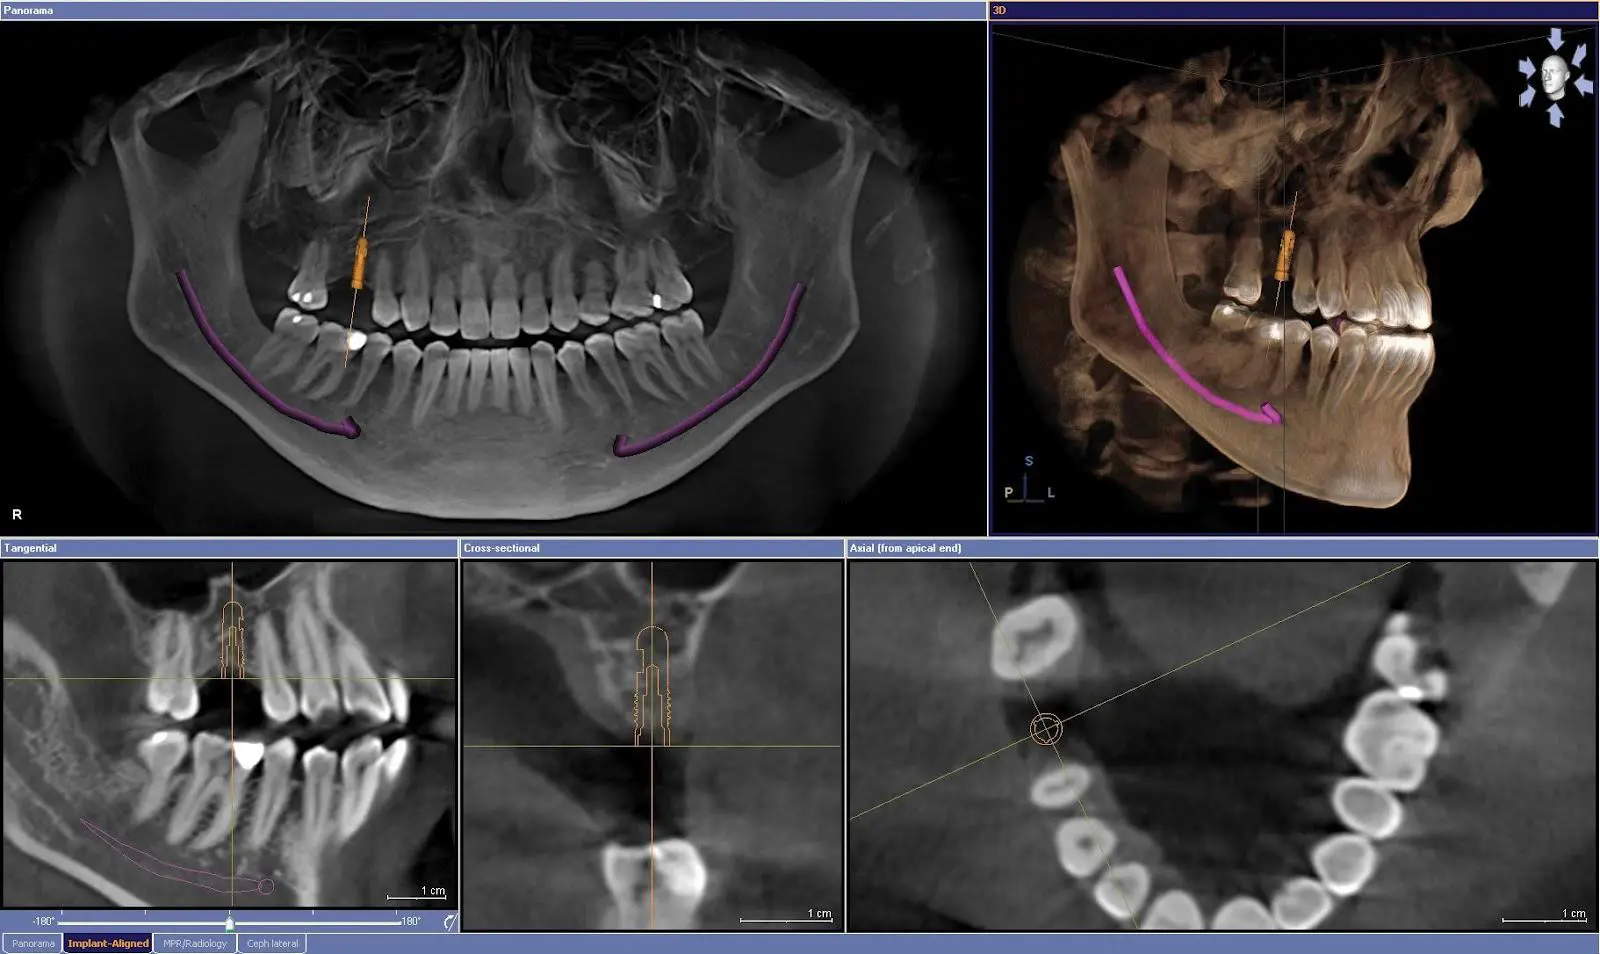

El tratamiento de implantología no consiste simplemente en colocar un implante dental. Se trata de un proceso clínico cuidadosamente planificado, en el que cada paso se estudia previamente para garantizar la máxima seguridad, estabilidad y predictibilidad del resultado. Antes de realizar cualquier intervención, el Dr. Balabanian evalúa el estado general de tu boca, la calidad y cantidad de hueso disponible, la posición de los dientes y la salud de las encías. En muchos casos también se realizan pruebas radiográficas o estudios en tres dimensiones que permiten planificar con precisión la posición del implante.

1 Diagnóstico completo

Realizamos un estudio clínico y radiológico para evaluar la calidad del hueso y planificar la posición exacta del implante en tu primera visita en Look Dental. Incluso disponemos de TAC 3D para casos más complejos.